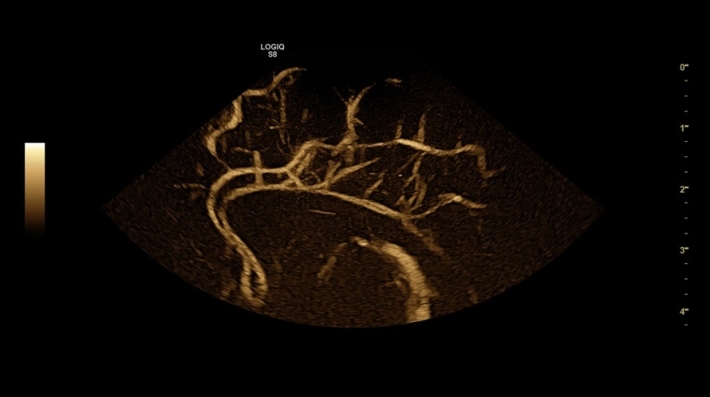

Ультразвуковой сканер Logiq S8 представляет собой инновационное устройство, которое сочетает передовые технологии, функциональные возможности и удобный интерфейс. Его основная цель — облегчить и ускорить процесс диагностики, сократив время обследования вдвое, при этом повышая точность и достоверность полученных данных.

Logiq S8 подходит для диагностики широкого спектра заболеваний и проведения исследований различных анатомических областей, включая брюшную полость, сердечно-сосудистую и скелетно-мышечную системы, молочные железы и другие органы.

• Real Time 4D Option — трехмерное сканирование в реальном времени;

• Tomographic Ultrasound Imaging (TUI) Option — программа получения томографических срезов объемного ультразвукового изображения;